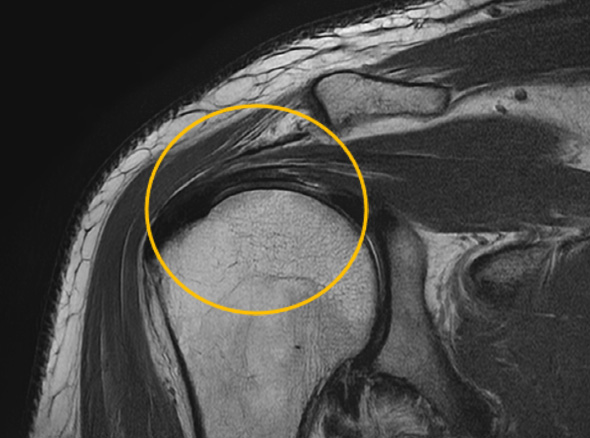

어깨충돌증후군이 발생하게 되면 회전근개에 염증이 발생하게 되고

급성 부종을 일으키게 됩니다.

회전근개 파열로 진행되고 있는 경우

관절 내시경을 통한

견봉 성형술

관절 내시경을 통하여

힘줄 손상을 유발하는 견봉하 골극을 제거합니다.